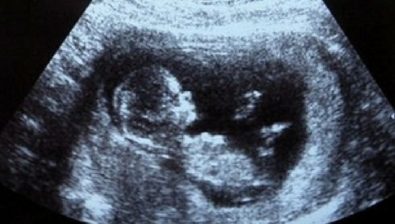

Ultrasound at 11 Weeks

Like mentioned before, the head makes up about half of your baby’s entire length. It is starting to uncurl from the body more than before. As the neck develops and gets longer, the chin seems to lift up from the chest.

One especially sweet formation is that fingernails now appear on your baby’s hands. Toenails will soon follow.

Although you might not know your baby’s gender for a while longer, he/she is slowly transforming into one gender or the other.

External male or female genitalia is more distinguished and will continue to develop in the coming months.